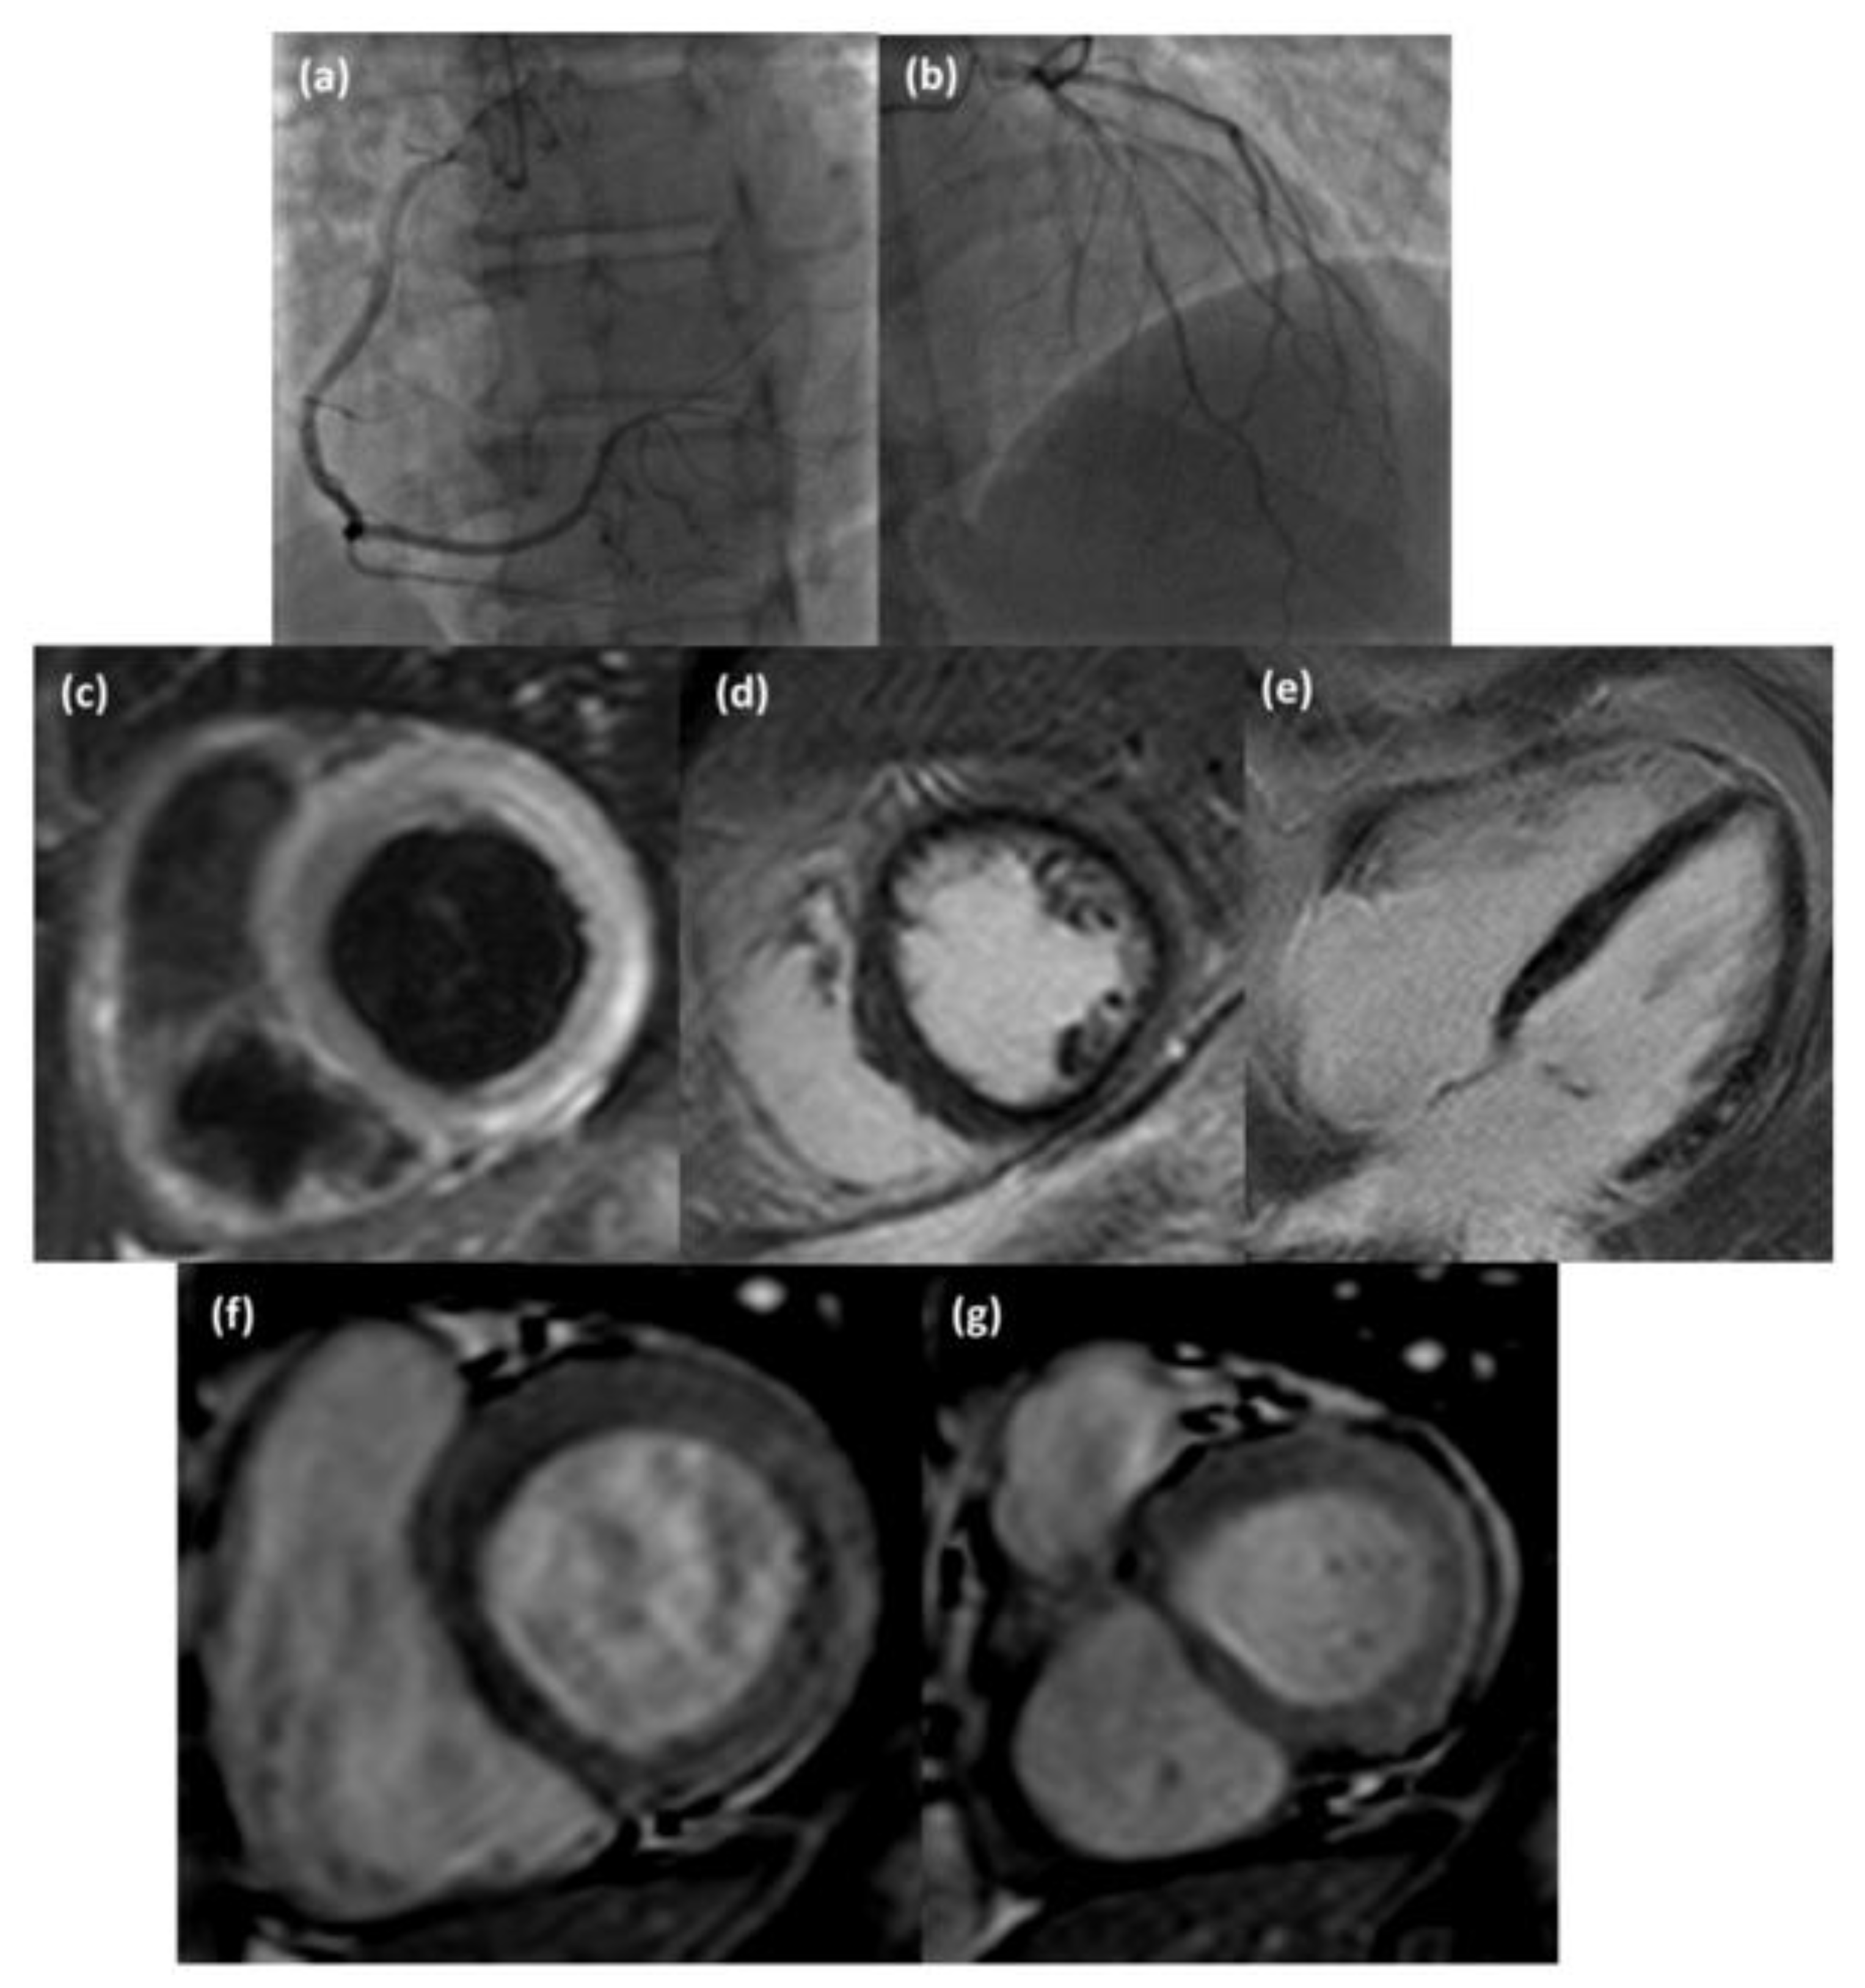

Figure 3.

Coronary angiography images (a,b) of a 42-year-old man suspected of acute coronary syndrome that did not show hemodynamically significant stenosis; CMR examination revealed the presence of subepicardial edema (T2-weighted STIR short axis view, (c)), subepicardial late gadolinium enhancement (inversion recovery T1-weighted short axis view, (d) and four chamber view, (e)) and hyperemia (cine steady-state free precession short axis view in diastol (f) and systole (g)) at the basal inferior-lateral wall of the LV.